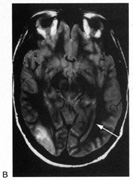

Achromatopsia in the contralateral hemifield alone can follow unilateral right or left occipital lesions (Fig. 18). Patients are typically asymptomatic until the defect is demonstrated on examination.234,235 Hemiachromatopsia is usually associated with a superior quadrantanopia;234,235,241 therefore, the color defect is only demonstrable in the remaining inferior quadrant. The preserved color vision in the ipsilateral hemifield allows normal or near-normal performance on centrally viewed tests of color vision such as pseudoisochromatic plates. The incidence of hemiachromatopsia is probably underestimated, given its asymptomatic nature and the failure of routine clinical color tests to detect its presence.

Fig. 18. Magnetic resonance imaging scan of patient with stroke causing a right hemiachromatopsia as well as partial superior quadrantanopia.